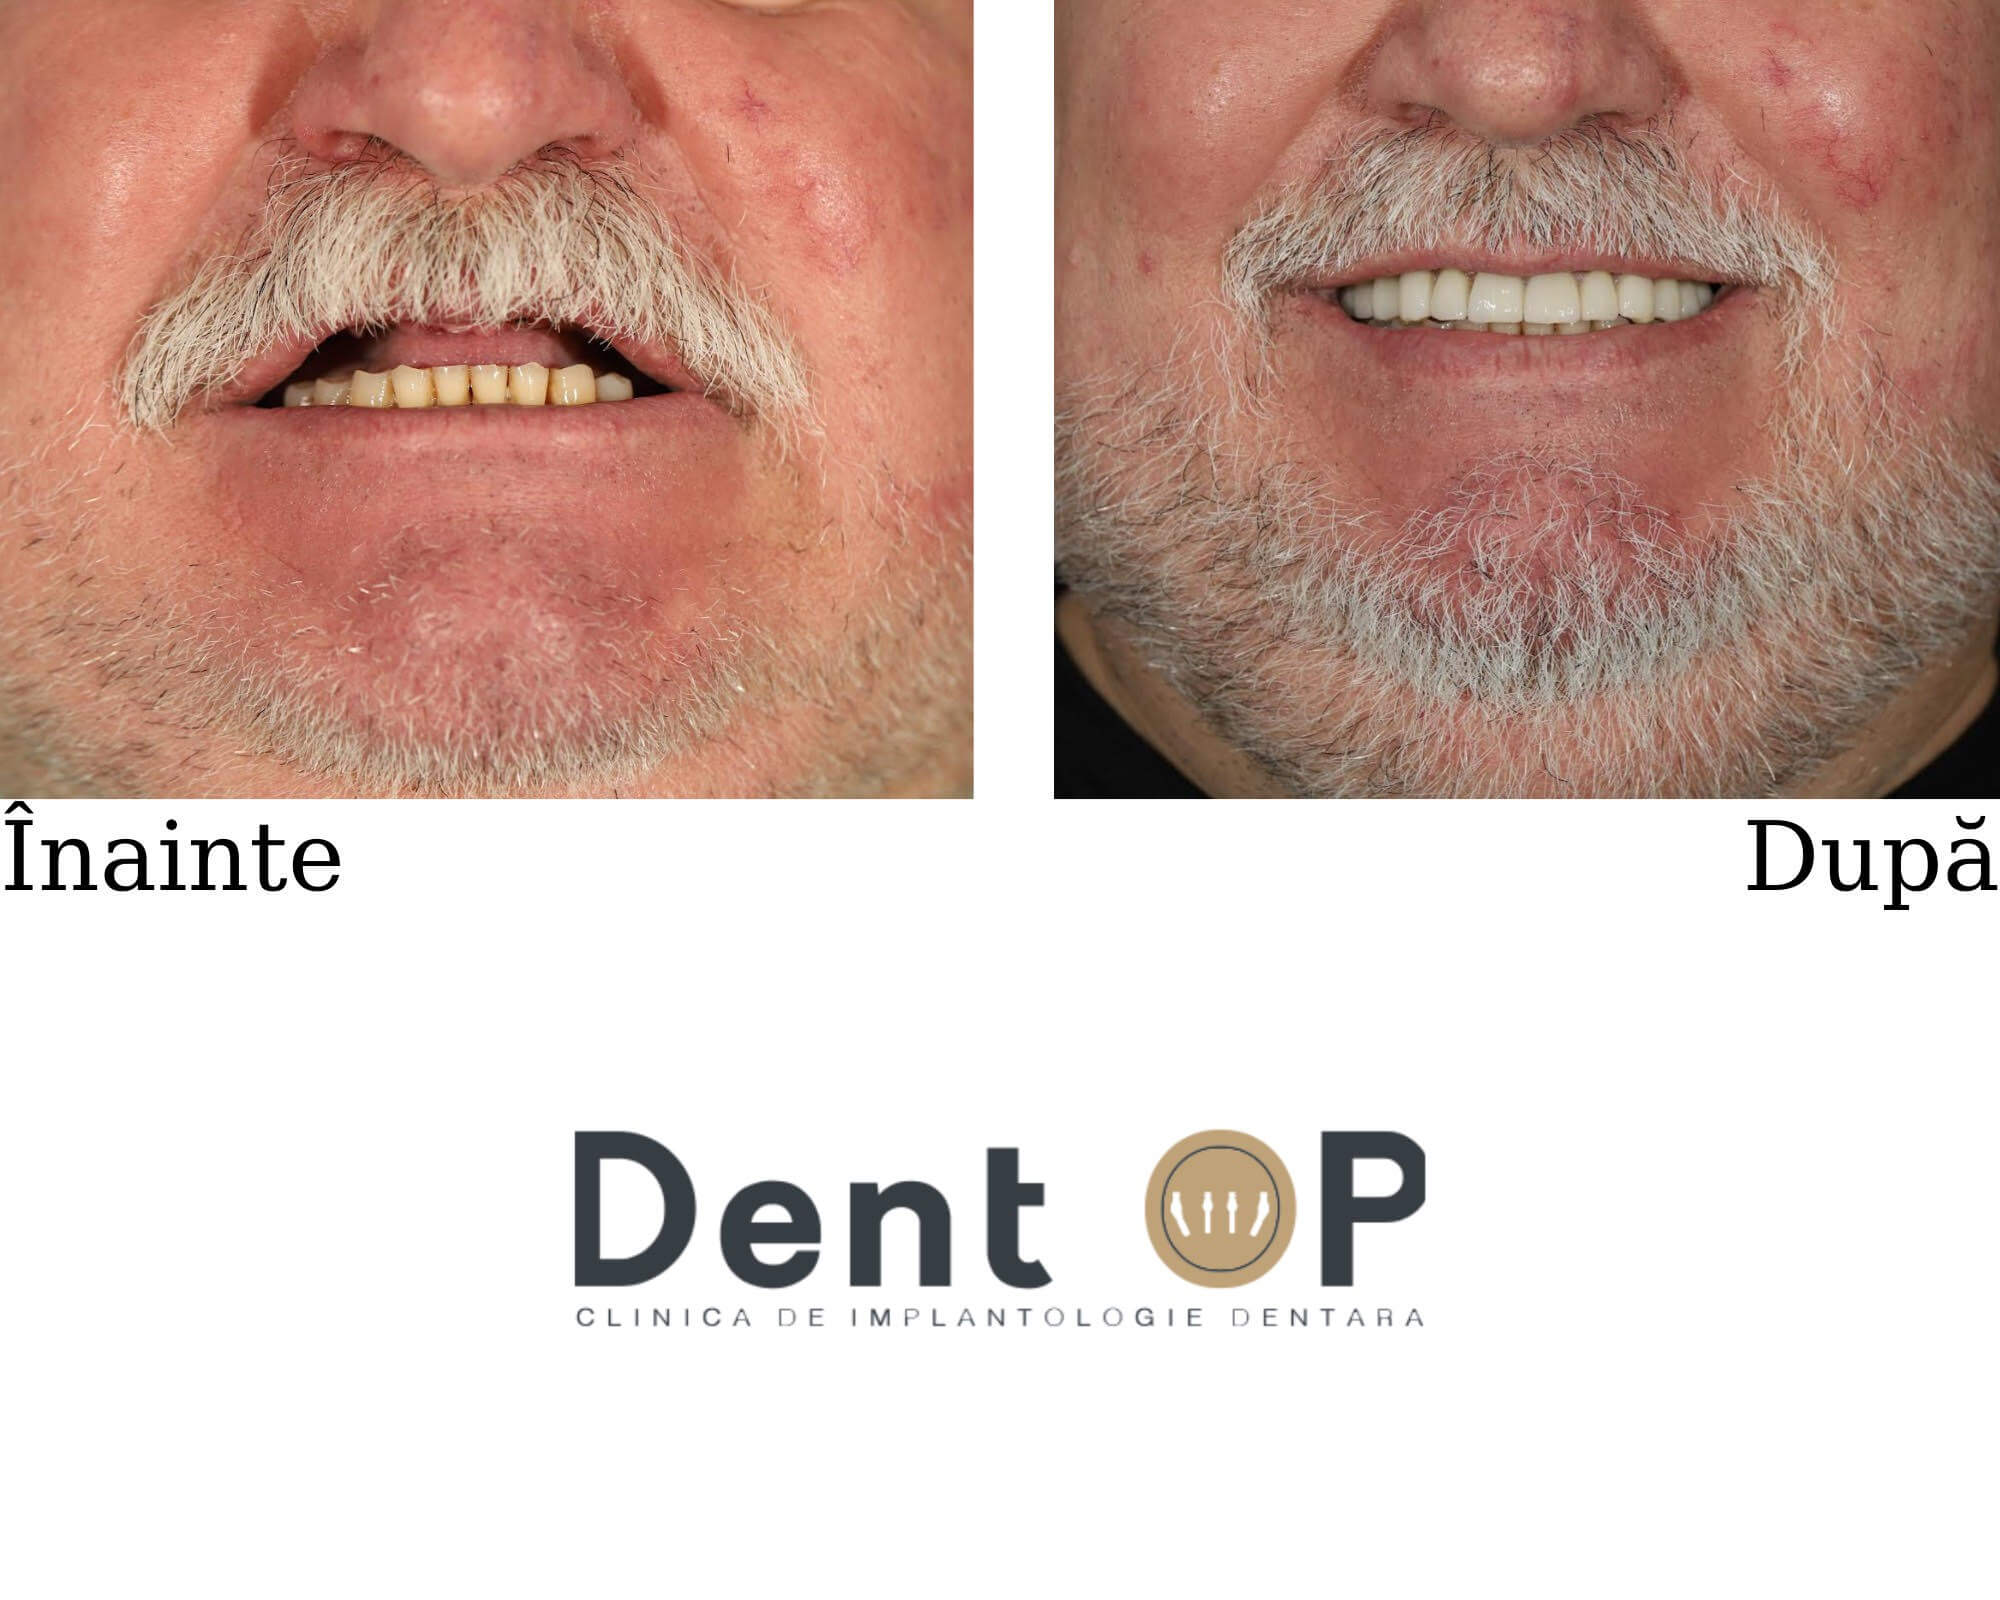

Cariile agresive l-au lăsat fără dantură. Dr Cazacu i-a propus un plan de tratament care să-i redea în totalitate zâmbetul și masticația

În urma unei consultații alături de Dr Cazacu Corrado, domnul S. a început un plan de tratament cu implanturi dentare. La maxilar, domnul S. nu mai avea niciun dinte din cauza cariilor agresive care i-au distrus dantura.

Dr Cazacu Corrado i-a propus un plan de tratament predictibil în urma consultației care a inclus inserarea a 9 implanturi dentare. Acestea au fost distribuite astfel : 6 la maxilar (pentru a realiza o dantură fixă) și 3 la mandibulă în poziții cheie pentru a completa dantura. Dinții care au putut fi salvați au fost păstrați.

La 24h de la procedura ,,Dantură Fixă în 24h pe implanturi dentare”, domnul S. a primit primele lucrări provizorii pe care le-a purtat timp de 6 luni. S-a prezentat la controalele periodice și a respectat cu strictețe indicațiile și astfel s-a putut vindeca rapid și eficient.

Alături de sfatul Medicului Protetician, pacientul a ales dantura potrivită pentru fizionomia și trăsăturile sale. Astfel în doar 24h a putut mânca și zâmbi, iar acum are o dantură impecabilă care îl ajută să aibă încredere în zâmbetul său.

Se bucură acum de un zâmbet frumos și sănătos pe care l-a obținut în scurt timp cu ajutorul implanturilor dentare.